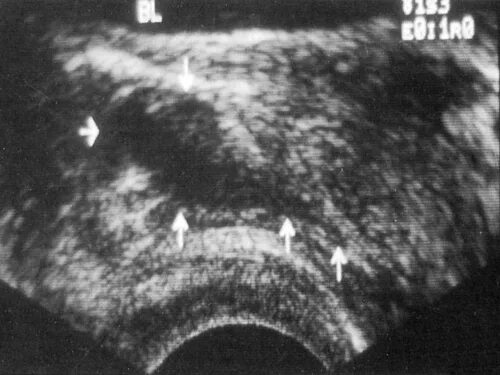

На фоне диффузных изменений